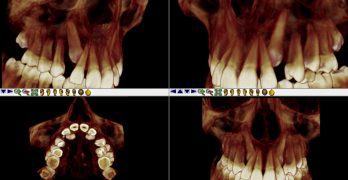

BDR CCCIV: Intrusión de un molar por medio de mini-tornillo para prótesis.

Ya es viernes, y el Baúl del Recuerdo lo sabe. Hoy traemos una nota llamada Intrusión de un molar sobreerupcionado por … [Leer más...] acerca de BDR CCCIV: Intrusión de un molar por medio de mini-tornillo para prótesis.